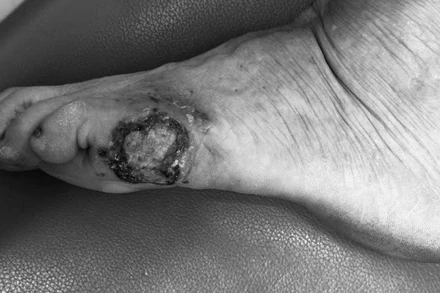

Bệnh viện Da liễu Trung ương vừa tiếp nhận một bệnh nhân nữ (68 tuổi), đến khám và điều trị tại bệnh viện, tổn thương là một mảng đen vùng cạnh ngoài bàn chân trái.

Tổn thương ung thư hắc tố của da nếu được phát hiện sớm và điều trị theo đúng phác đồ thì cho kết quả tốt, giảm tỷ lệ di căn xa và tỷ lệ sống 5 năm rất cao.

Sau khi đi nhiều cơ sở y tế điều trị tình trạng ngón chân bị đen thâm, bệnh nhân được phát hiện mắc ung thư tế bào hắc tố tại Bệnh viện Da liễu Trung ương.

Chuyên gia da liễu cảnh báo, ung thư da có thể phát sinh từ các tế bào hắc tố của da nhưng có khả năng xâm lấn sâu xuống các lớp da bên dưới và di căn sớm theo đường bạch huyết hoặc đường máu đến các cơ quan như hạch bạch huyết, phổi, gan và não.